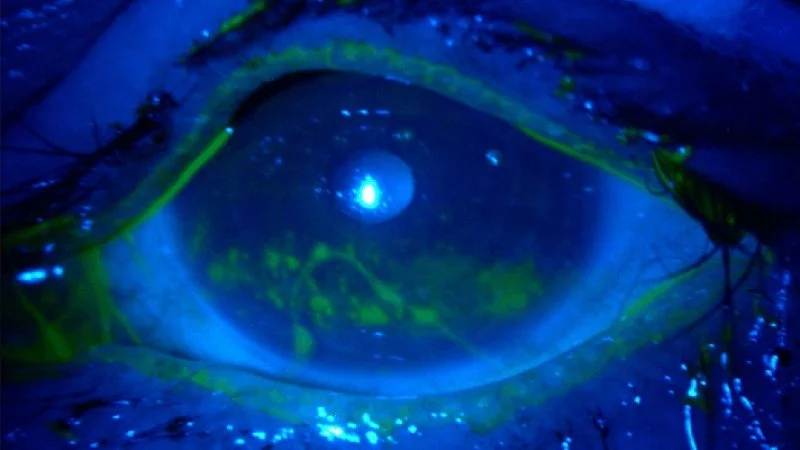

Corneal transplantation is a procedure in which a damaged or diseased cornea is removed and replaced with healthy donor tissue. This operation is often referred to as a corneal graft or keratoplasty. It can be used to restore vision, treat severe infections, repair damage, and relieve pain.

Corneal transplants are usually performed to correct vision problems that have developed as a result of certain medical conditions.

Some of the most common reasons for undergoing a corneal transplant include: